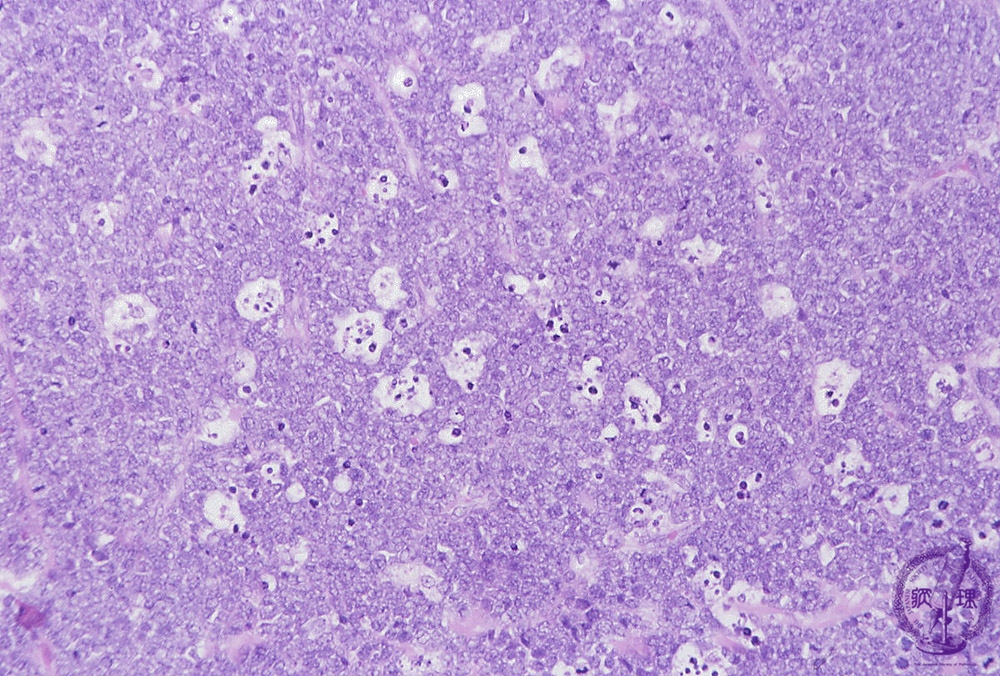

Microscopic image (H&E low power view): Amongst the neoplastic lymphocytes are scattered tangible body macrophages. The clear cytoplasm of the latter cells juxtaposed with densely packed, darkly staining neoplastic lymphocytes conjures images of a gstarry skyh, an apt term which is often used to describe Burkitt lymphoma.